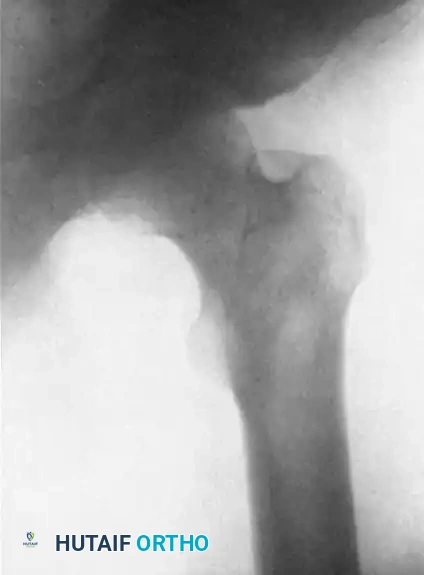

Image

FIGURE 61-3 B: The same hip on the fifth day of heavy skeletal traction. The massive longitudinal force has successfully overcome the soft-tissue contractures, bringing the head of the femur partially below the level of the acetabular roof.

1. Abduction and Weight Reduction: Once the head is at the level of the acetabulum, the limb is gradually abducted. This abduction uses the intact anterior capsule (iliofemoral ligament) as a hinge to lever the femoral head laterally and anteriorly over the posterior rim of the acetabulum. Simultaneously, the traction weight is reduced by 3.6 kg every fourth day to prevent over-distraction of the joint.